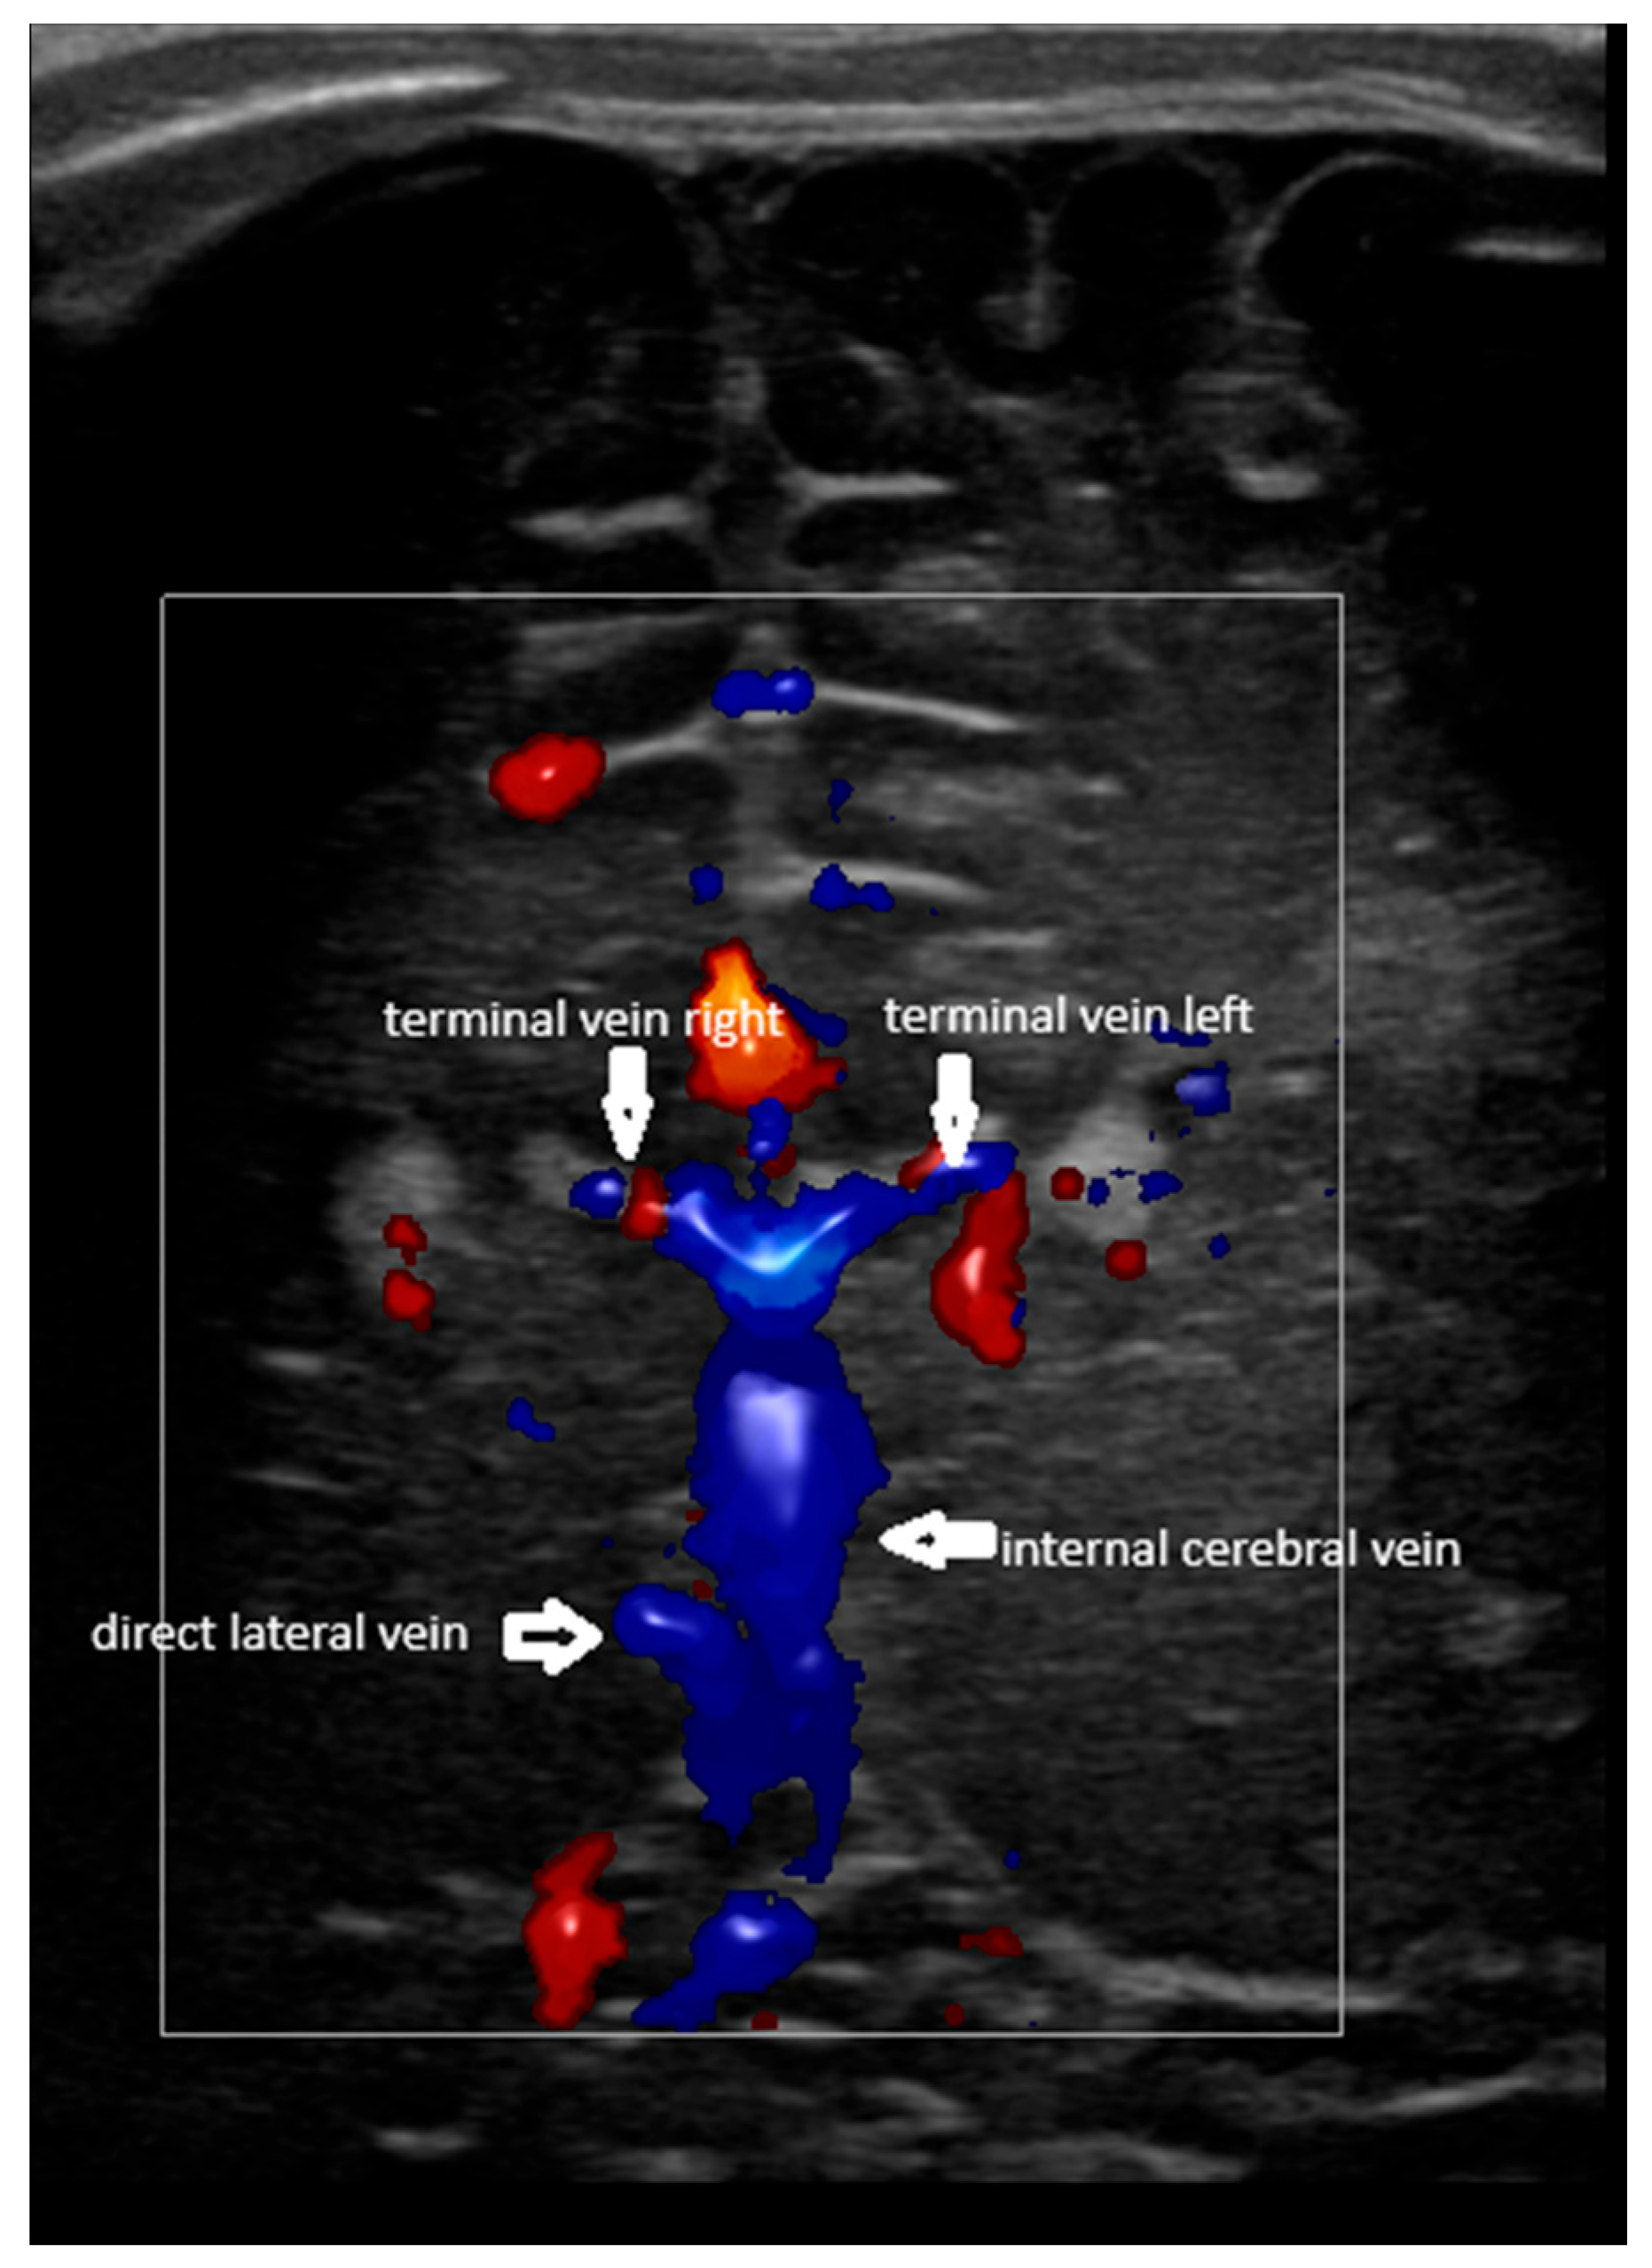

- Confluence posterior to the foramen of Monro, the most frequent variant (Figure 1).

- A lack of identification of the confluence—wherein the terminal vein was absent on one or both sides—an example is the case presented in Figure 3, where the terminal vein was most probably draining in a direct lateral vein on the left side.